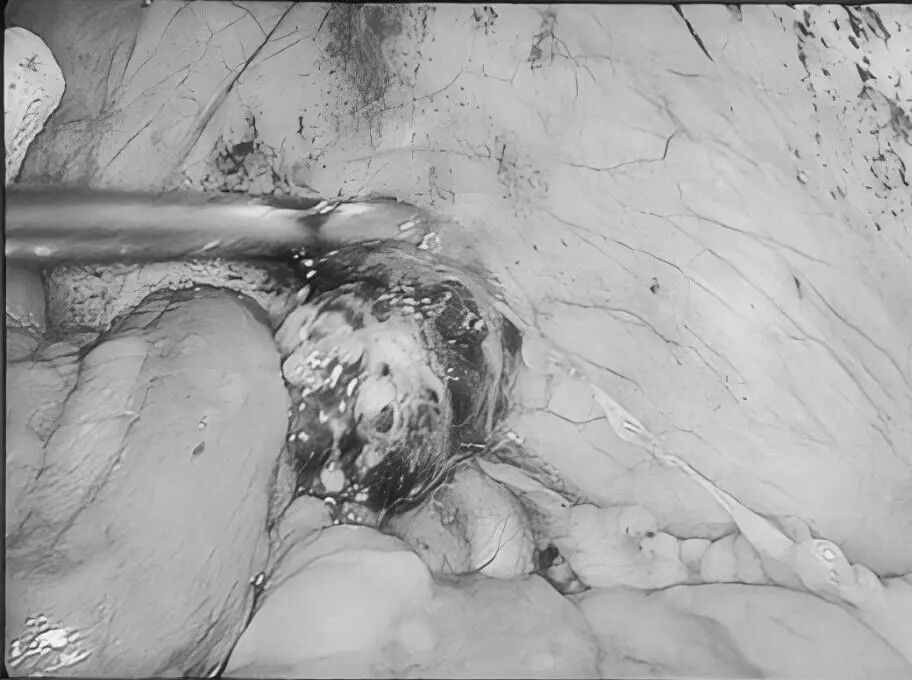

无数次立下减肥的誓言 尝试过五花八门的减肥方法 节食饿得头晕眼花 运动累得精疲力竭 但体重却像坐过山车 稍有松懈 就迅速反弹 别担心 或许减重手术 就是改变您体重的 关键契机 当前,肥胖已不仅仅是关乎外貌美观的问题,更像是一颗隐藏在身体里的定时炸弹,悄然引发各种慢性疾病。对于重度肥胖朋友来说,传统的饮食控制和运动往往收效甚微。而减重手术,为肥胖人群重获健康与自信带来了新的选择。 什么是减重手术? 减重手术,也被称为代谢手术,主要是对消化系统进行 “重塑”。目前,常见的手术方式有腹腔镜袖状胃切除术、腹腔镜胃旁路术及胃束带手术等。 比如,通过缩小胃容量,让您进食少量食物就有饱腹感,或者改变消化道结构,减少身体对营养的过度吸收。 胃旁路手术 袖状胃切除术 胃束带手术 减重手术真的有效果吗? 减重明显,告别肥胖 接受减重手术后,一般1到2年内,可以减掉超重体重的 60%-80%,让您告别肥胖困扰。 改善代谢,减少疾病 能够有效缓解Ⅱ型糖尿病、高血压、高血脂等肥胖相关疾病,让您重新拥有健康的身体状态。 减重手术,适合哪些人? 减重手术并非人人适用,需要经过严格、专业的术前评估。一般来讲,如果体重指数(BMI)≥30kg/m²,或者 体重指数(BMI)≥25 kg/m² 且合并有严重代谢性疾病,那么就可以将减重手术纳入考虑范围。 普外科专家简介 梁 跃 中共党员,普外科党支部书记、主任,主任医师 临床擅长:对普外科各类肿瘤手术具有丰富的临床经验。 毕业于遵义医学院,遵义市医学会小儿外科学分会常务委员,遵义市肛肠协会理事,遵义市医学会核医学分会(第二届)委员会委员;荣获第三期“黔医人才计划”优秀学员称号;主持市级课题1项,完成省级课题1项,在国内各类刊物上发表论文10余篇。 钱科洪 普外科副主任医师 临床擅长:从事普外科临床工作30余年,对各类普外科疾病的诊治、乳腺、甲状腺、胃十二指肠、结直肠等疾病及疑难杂症具有丰富的临床诊疗经验。 毕业于遵义医学院临床医疗系,2009年前往中山大学附属第一医院微创外科进修学习,在国内各专业期刊发表论文数篇。 贵州航天医院普外科简介 基本情况 贵州航天医院普外科成立于19世纪60年代,前身属于原航天部O61基地3417医院外一科,1998年更名为普外科,下设胃肠外科、肛肠外科2个亚专业科室,拥有专科设备和技术,是中国疝病专科联盟单位,贵州医科大学附属医院胃肠外科专科联盟单位。开放床位40张,配备医护人员21人。 专科特色 普外科致力于胃肠及肛肠疾病的外科临床诊治及科研,以腹腔镜微创外科技术为本,形成以快速康复治疗胃肿瘤、结直肠肿瘤、小肠肿瘤、直肠脱垂、肥胖病、急腹症、各类疝、痔、瘘等专科特色,同时注重胃肠疾病尤其是结直肠恶性肿瘤的基础研究和临床转化研究。 开展手术:腹腔镜下胃癌根治术,腹腔镜下袖状胃切除术,腹腔镜下胃肠道间质瘤切除术,腹腔镜下结、直肠癌根治术,胃癌、结直肠癌的精准治疗,腹腔镜下小儿疝气、成人疝修补术,腹腔镜下阑尾手术,内痔的硬化注射治疗及痔疮的微创治疗:ATH、PPH、TST,直肠脱垂的各种手术治疗,难治性伤口VSD技术,鼻胃肠管、肠梗阻导管置入术,肛肠术后间歇性导尿技术,并引进了中医适宜技术,也为各种化疗患者提供输液港安装,提高患者就医体验。 腹腔镜下腹股沟疝无张力修补术 腹腔镜下腹股沟疝 无张力修补术 腹股沟疝里金斯坦(Lichtenstein)手术 PPH微创术治疗环状混合痔 黏连性或炎性肠梗阻-肠梗阻导管 腹腔镜袖状胃切除 腹腔镜阑尾 切除术 腹腔镜阑尾肿瘤 切除术 腹腔镜下结肠癌根治术 诊疗范围 胃肿瘤、结直肠肿瘤、小肠肿瘤、肥胖症、各类急腹症、腹部外伤、腹壁疝、便秘、直肠脱垂、痔疮、肛瘘、肛裂等胃肠、肛肠外科疾病。 END